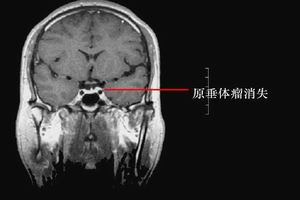

2.影像學檢查(CT、MRI)腫瘤直徑<5mm者,CT較難發現。正常垂體高2~7mm,女性如>7mm,男性>5mm即有腫瘤可能。

3.頭顱MRI正常人垂體前葉MRI信號與腦灰質相似,神經垂體95%呈短T1高信號,垂體上緣多呈下凹偏平,少數偶見平緩的微凸狀,明顯的局部上凸者90%為垂體微腺瘤。正常垂體柄居中,小於4mm,垂體柄移位是垂體病變的間接指征。MRI診斷垂體大腺瘤效果等於或優於頭顱CT,能清楚的辨別垂體瘤與視神經視交叉的關係。一般MRI診斷垂體微腺瘤不如頭顱CT,但近年用1.5T高場強MRI掃描對垂體微腺瘤診斷的敏感性提高到83%,而頭顱CT僅為42%,以冠狀面和矢狀面影像最清楚。在T1加權像上呈局灶性低信號,在T2加權像上呈局灶性高信號,其特點表現:冠狀面垂體上緣局限性上凸,垂體腺高度增加,鞍底向下膨隆,雙側頸內動脈海綿竇段不對稱,病灶處向外下移位,強化後即刻掃描顯示微腺瘤呈局灶低信號,而正常垂體明顯強化。MRI對顱咽管瘤的定性診斷不如CT,頭顱CT可顯示典型的鈣化灶,而MRI顯示鈣化效果欠佳,MRI的主要依據是:位於鞍上區是囊性腫物,增強後囊壁可呈環狀加強。